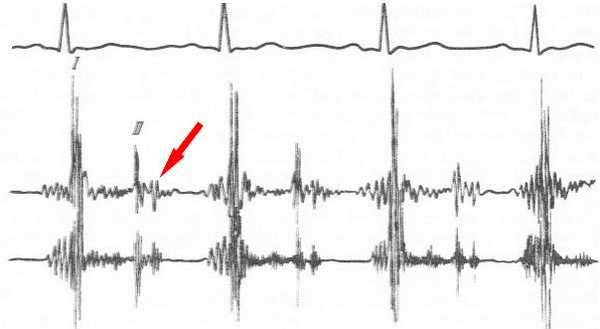

ритм перепела на ФКГ

Для уточнения характера патологических тонов в сердце используется фонокардиография (ФКГ) - исследование, при котором с помощью микрофона усиливаются звуки тонов, а затем преобразуются в графическое изображение при помощи писчего устройства. ФКГ интерпретируется специалистом и помогает достоверно выяснить, чем обусловлены патологические звуковые феномены. Часто ФКГ проводится детям при подозрении на порок сердца.